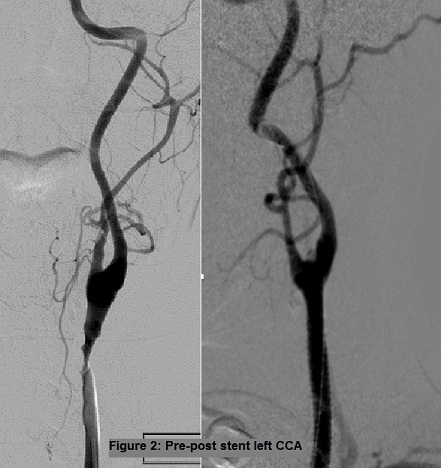

Percutaneous arterial access was achieved from right common femoral artery and a 90 cm, 8 Fr sheath was placed. An 8 Fr sheath was advanced to the descending thoracic aorta over a 0.035 super stiff angled glide wire. A 6 Fr vertebral catheter was advanced through the sheath over wire into the right External Carotid Artery (ECA). The wire was removed and exchanged for a 0.035, 260 cm stiff Amplatz wire and 8 Fr sheath was advanced into the right CCA. The stiff Amplatz was exchanged for a 0.018, 300 cm. A 5 cm long Viabahn stent graft (WL Gore and Associates) was placed with the distal end just proximal to the ECA origin and extended proximally. Post-dilation was then performed using an 8x40mm diameter. Diagnostic angiography showed successful exclusion of the pseudoaneurysms and a widely patent ECA and ICA (Figure 1). There were no neurological or other complications.

Figure 1: Pre-post stent right CCA.